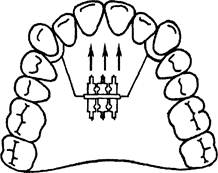

Рис. 13.38. Пластинка на верхнюю челюсть для трансверсального расширения переднего участка верхнего зубного ряда.

Сила давления протрагирующей пружины должна быть направлена перпендикулярно к оси зуба, так как иначе при активации пружина будет соскальзывать к режущему краю зуба. На рис. 13.42 изображена протрагирующая дуга, которая позволяет орально расположенные зубы перемещать в вестибулярном направлении.